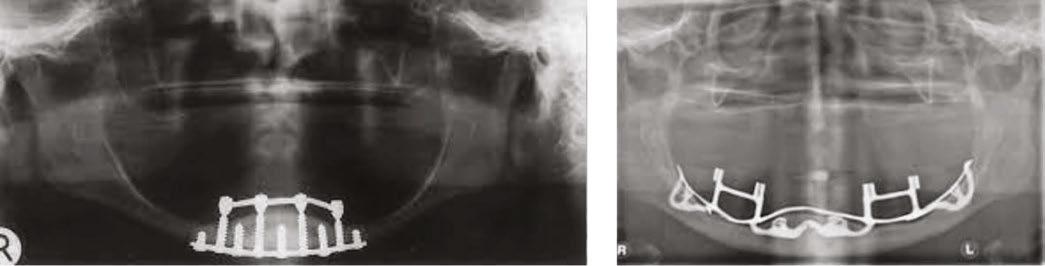

The use of dental implants to replace missing teeth is causing a revolution in dental care. A dental student or dental resident in the 1970s learned about “new” techniques such as transmandibular staple-type implants1 or subperiosteal implants2 to support a removable overdenture (Figures 13A and 13B). These were invasive treatments that were confined to specialist’s practice. These early implant patients only enjoyed a moderate increase in comfort and function. This was a poor outcome for the time and expense involved.

In the 1970s and early 1980s, the surgery was extensive, painful, and the failure of these modalities was catastrophic for the patient. Photos like Figures 13A and 13B remind us how far the science and technology of implant treatment has come in a brief period. The best we can do for our patients is to put their interests first, offer clear choices, and provide evidence-based dental treatment (Figure 14).

2. Paton G, Fuss J, Goss AN. The transmandibular implant: a 5- and 15-year single-center study. J Oral Maxillofac Figure 14. Post implant placement. This CBCT shows implant at site 10 through the impacted canine. Implant at site 3 was placed right against the sinus floor Figures 13A and 13B: 13A. Trans-mandibular dental implants. 13B. Subperiosteal implants Figure 11: Surgical site on day of surgery Figure 12: Implant placement of tooth No. 7 with buccal bone graft